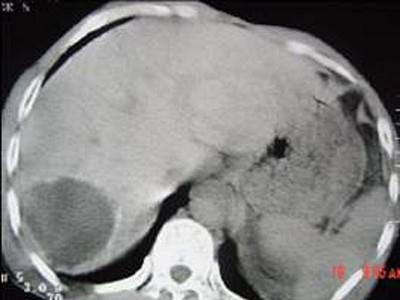

问题 女,62岁,右上腹隐痛,曾在新疆生活30余年,有犬、羊密切接触史,CT平扫如图,最可能的诊断是 ( )

选项 A、肝血管瘤 B、肝包虫病 C、肝癌 D、肝脓肿 E、肝囊肿

答案 B